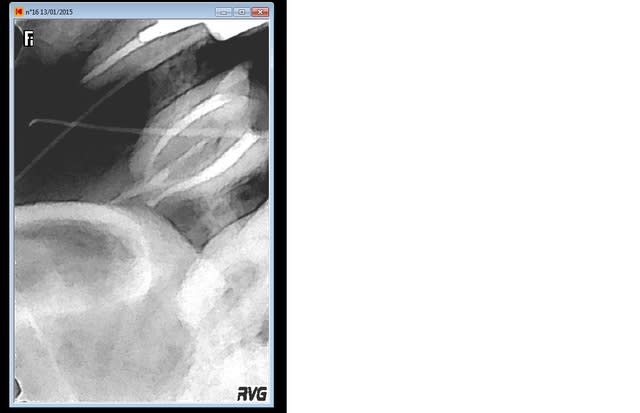

J'essaye de reprendre le MV2 quand meme: ma lime progresse et je bloque à un moment.

du coup, je fais une radio lime en pace. et là: je crois que je suis dans un faux canal. Moi, les faux canaux, j'arrive jamais à les passer. j'obuture donc là ou je juis après avoir bien irrigué.

Je prends alors des radios avec les 2 cones de guttas dans chaque fistule. JE les enfonce à fond, et le trouve la première radio (les 2 cones se rejoignent).

j'enlève le capteur, verifie que les cones sont bien à fond et qu'ils ont pas bougés, et là: surprise, ils peuvent à nouveau s'enfoncer. je pense que j'aurais pu les mettre jusqu'à la garde.... 2 eme radio.

Mv2 wva7f5 - Eugenol

Cones gutta 1 pkfu1s - Eugenol

Cones gutta 2 jhnnyy - Eugenol